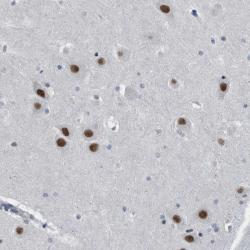

- Immunohistochemical staining of human hippocampus shows strong nuclear positivity in neuronal cells.

- Staining pattern partly consistent with experimental and/or bioinformatic data.